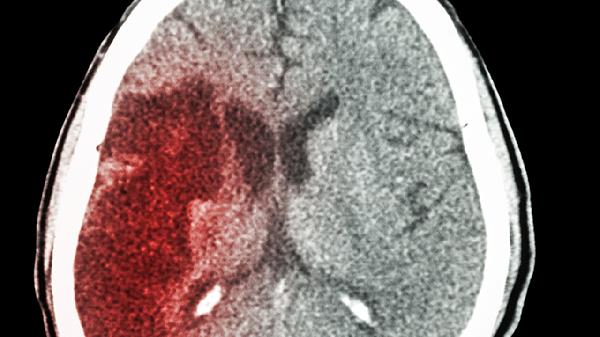

摔跤后出现脑出血有哪些明显症状

摔跤后引发脑出血的常见表现包括头痛、呕吐、意识不清、肢体无力以及瞳孔变化等。这种状况可能由外伤、高血压或脑血管结构异常等...